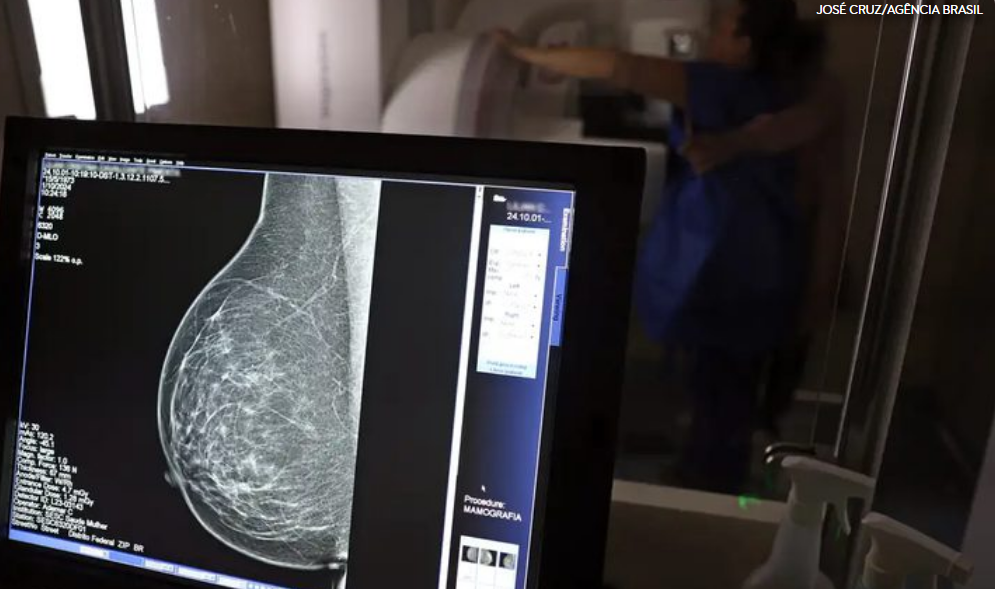

Até então, o rastreamento era indicado a partir dos 50 anos. A atualização foi definida porque, segundo o Ministério da Saúde, a faixa etária dos 40 aos 49 anos concentra aproximadamente 23% dos casos de câncer de mama no Brasil. Além disso, houve ampliação da idade máxima para o exame: se antes era recomendado até os 69 anos, agora se estende até os 74 anos. Na Rede Ebserh , 24 hospitais ofertam mamografia. Somente no ano de 2024 , foram realizados mais de 54 mil exames.

O mastologista do Hospital de Clínicas da Universidade Federal de Uberlândia (HC-UFU), Donizete Willian Santos, afirma que “o diagnóstico precoce, principalmente com o rastreamento mamográfico, pode diminuir a mortalidade pelo câncer de mama em até 40% quando iniciado aos 40 anos na população de baixo risco. Além disso, reduz a necessidade de quimioterapia e o tempo em terapias complementares, como o bloqueio hormonal”.

Para o especialista, o autoconhecimento do corpo continua sendo um aliado importante. No Brasil, apenas 37% das mulheres em idade alvo realizam a mamografia, enquanto a recomendação da Organização Mundial da Saúde (OMS) é de 70%. “Embora o autoexame não diminua a mortalidade, ele conscientiza a mulher sobre a necessidade de realizar a mamografia e pode levá-la a procurar o serviço de saúde mais cedo, melhorando muito os resultados oncológicos”, explica.